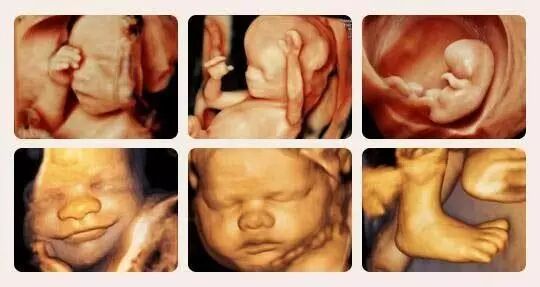

四维彩超不仅仅是感觉胎宝宝的呼吸和运动,还能亲眼目睹他们的一举一动和乖巧的秀容。强大的拍摄功能,在做四维彩超时,四维彩超能抓捕胎儿的每个细小的动作,将它制作成影集,为胎儿留下珍贵的“0”岁相片。

温江圣母妇产医院引进GE-E8高清四维彩超机,图片质量清晰,能显著提高图像的质量,可清晰地显示眼、鼻、口、下颔等状态,能多角度、多方位地对胎儿的体表进行检查,为医师判断宝宝是否畸形,提供科学有力的依据。